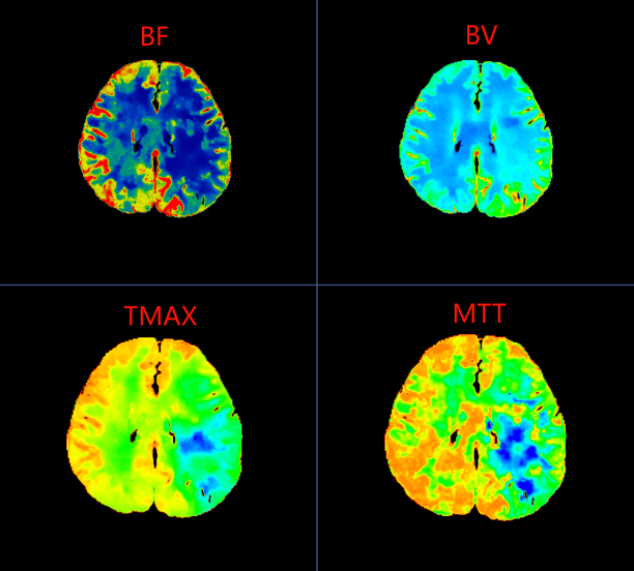

在脑梗死真正形成之前,大脑其实已经历一系列血流代偿与失代偿的过程。CTP(CT脑灌注成像)正是一种能够可视化脑血流动力学状态的前沿影像技术。它不仅能显示血管结构,更能精准评估脑组织的血流速度、血流量与血流通过时间,从而在患者尚未出现典型脑梗死症状时,就捕捉到脑灌注异常的“蛛丝马迹”。

李女士的CTP图像中,左侧大脑中动脉供血区呈现的“低灌注”表现,正是脑血流代偿机制开始崩溃的标志。这种梗死前的影像预警,为临床实施超早期干预——如强化抗血小板治疗、控制血压、改善脑灌注等——提供了至关重要的依据,从而有可能阻断病情进展,避免梗死发生。